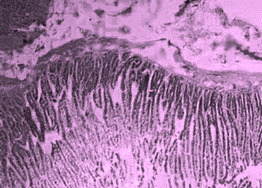

All the animals were observed daily for clinical signs of toxicity and morbidity. Individual animal body weights were recorded at receipt (on day 1) and weekly thereafter and at the time of sacrifice (fasting body weights). Histological examinations of various organs (brain, kidney, liver, small intestine and stomach) were carried out after 28 d using haematoxylin and eosin as staining agents. The organs were preserved in 10 % formalin solution.

On administration of TPSY, the animals in all groups were found to survive at the end of 28 d of study. The histological results are shown in table 4. Liver tissue showed minimal degeneration of hepatocytes compared to control at the highest dose of 350 mg which was however reported to be non-toxic.

Mild tubular degeneration was observed in kidneys Stomach tissue displayed moderate changes compared to control, with minimal degeneration of mucosal cellsat highest dose of 350 mg. Large intestine showed marked submucosal edema but the mucosal tissue appeared to be normal at the highest dose of 350 mg. No abnormality was observed in brain tissues at a low and medium dose. Mild submucosal edema was observed at 350 mg/kg. These results point to the negligible toxicity associated with the thiolated polymer and hence it can be considered to be safe for use as a pharmaceutical excipient.

Table 4: Histological results of repeated dose toxicity studies of TPSY (n=5)

| Organs | Normal saline | TPSY dose strength | ||

| Control | 70 mg/kg | 175 mg/kg | 350 mg/kg | |

| Liver | Normal architecture of liver, nothing abnormal detected. | Nothing abnormal detected. | Minimal degeneration of hepatocytes. | Minimal degeneration of hepatocyte and infiltration of inflammatory cells. |

| Kidney | Normal architecture of kidney, nothing abnormal detected. | Minimal tubular degeneration. | Mild tubular degeneration and congestion of blood vessels. | Mild tubular degeneration. |

| Stomach | Normal architecture of Stomach, Nothing abnormal detected. | Minimal degeneration of mucosal lining cells. | Mucosal cells were enlarged and were darkly stained. | Minimal degeneration of mucosal cells, accumulation of dark staining material in the gland. |

| Brain | Normal architecture of the brain, Nothing abnormal detected. | Nothing abnormal detected. | Nothing abnormal detected. | Minimal neuronal degeneration. |

| Large intestine | Papillary projections with goblet cells. | Mucosal lining no infiltration of inflammatory cells. | Minimal infiltration of inflammatory cells and congestion. | Marked submucosal edema, mucosal tissue appears normal. |

Fig. 8: Histology of various tissues at highest dose strength of 350 mg/kg body weight